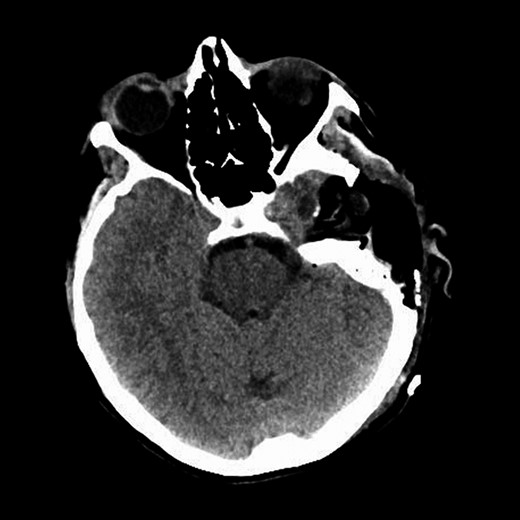

Repeat magnetic resonance imaging (Figs. 3 and 4) showed increased left-sided carotid PGL, significant extension into the jugular foramen and skull base, and associated high-grade tumor compromise of the left internal carotid artery; no radiologic evidence suggested intracranial ischemic sequelae. Computed tomographic (CT) imaging showed infiltration of the left petrous and clivus regions of the skull (Fig. 5). Findings were compatible with progression of the previously known tumor.

CT of the head with contrast, transverse section demonstrating infiltration of left petrous and clivus regions of skull.